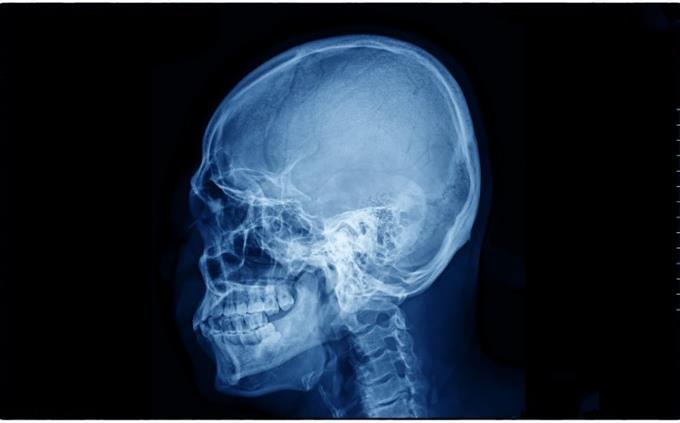

Medical imaging has transformed modern medicine, allowing physicians to look inside the human body without a single incision. From the accidental discovery of X-rays in the 19th century to today’s ultra-high-resolution MRI scanners and hybrid PET-CT systems, these technologies have revolutionized diagnosis, prevention, and treatment planning. But how well do you really understand what each scan can-and cannot-do? This quiz explores the science, history, strengths, limitations, and surprising nuances of medical imaging. Designed for seasoned minds who appreciate depth and detail, this challenge goes beyond basics. Let’s see how sharp your diagnostic instincts really are.

Who is credited with discovering X-rays in 1895?

Wilhelm Röntgen